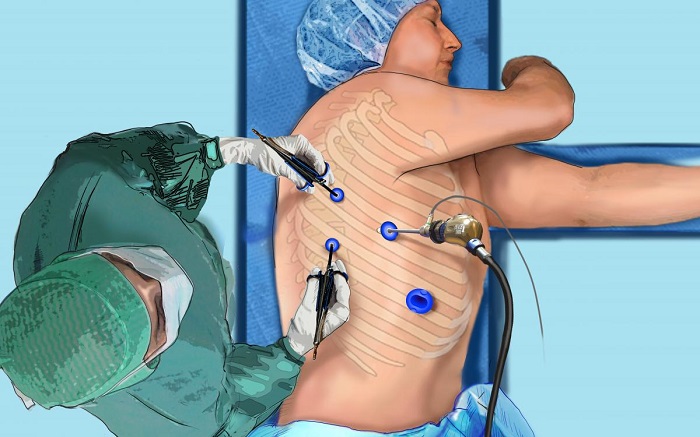

Specialist in Tuberculosis, Asthma, COPD, ILD, Pneumonia, Allergy, Bronchoscopy, Chest Diseases, Critical Care, and Sleep Disorders.